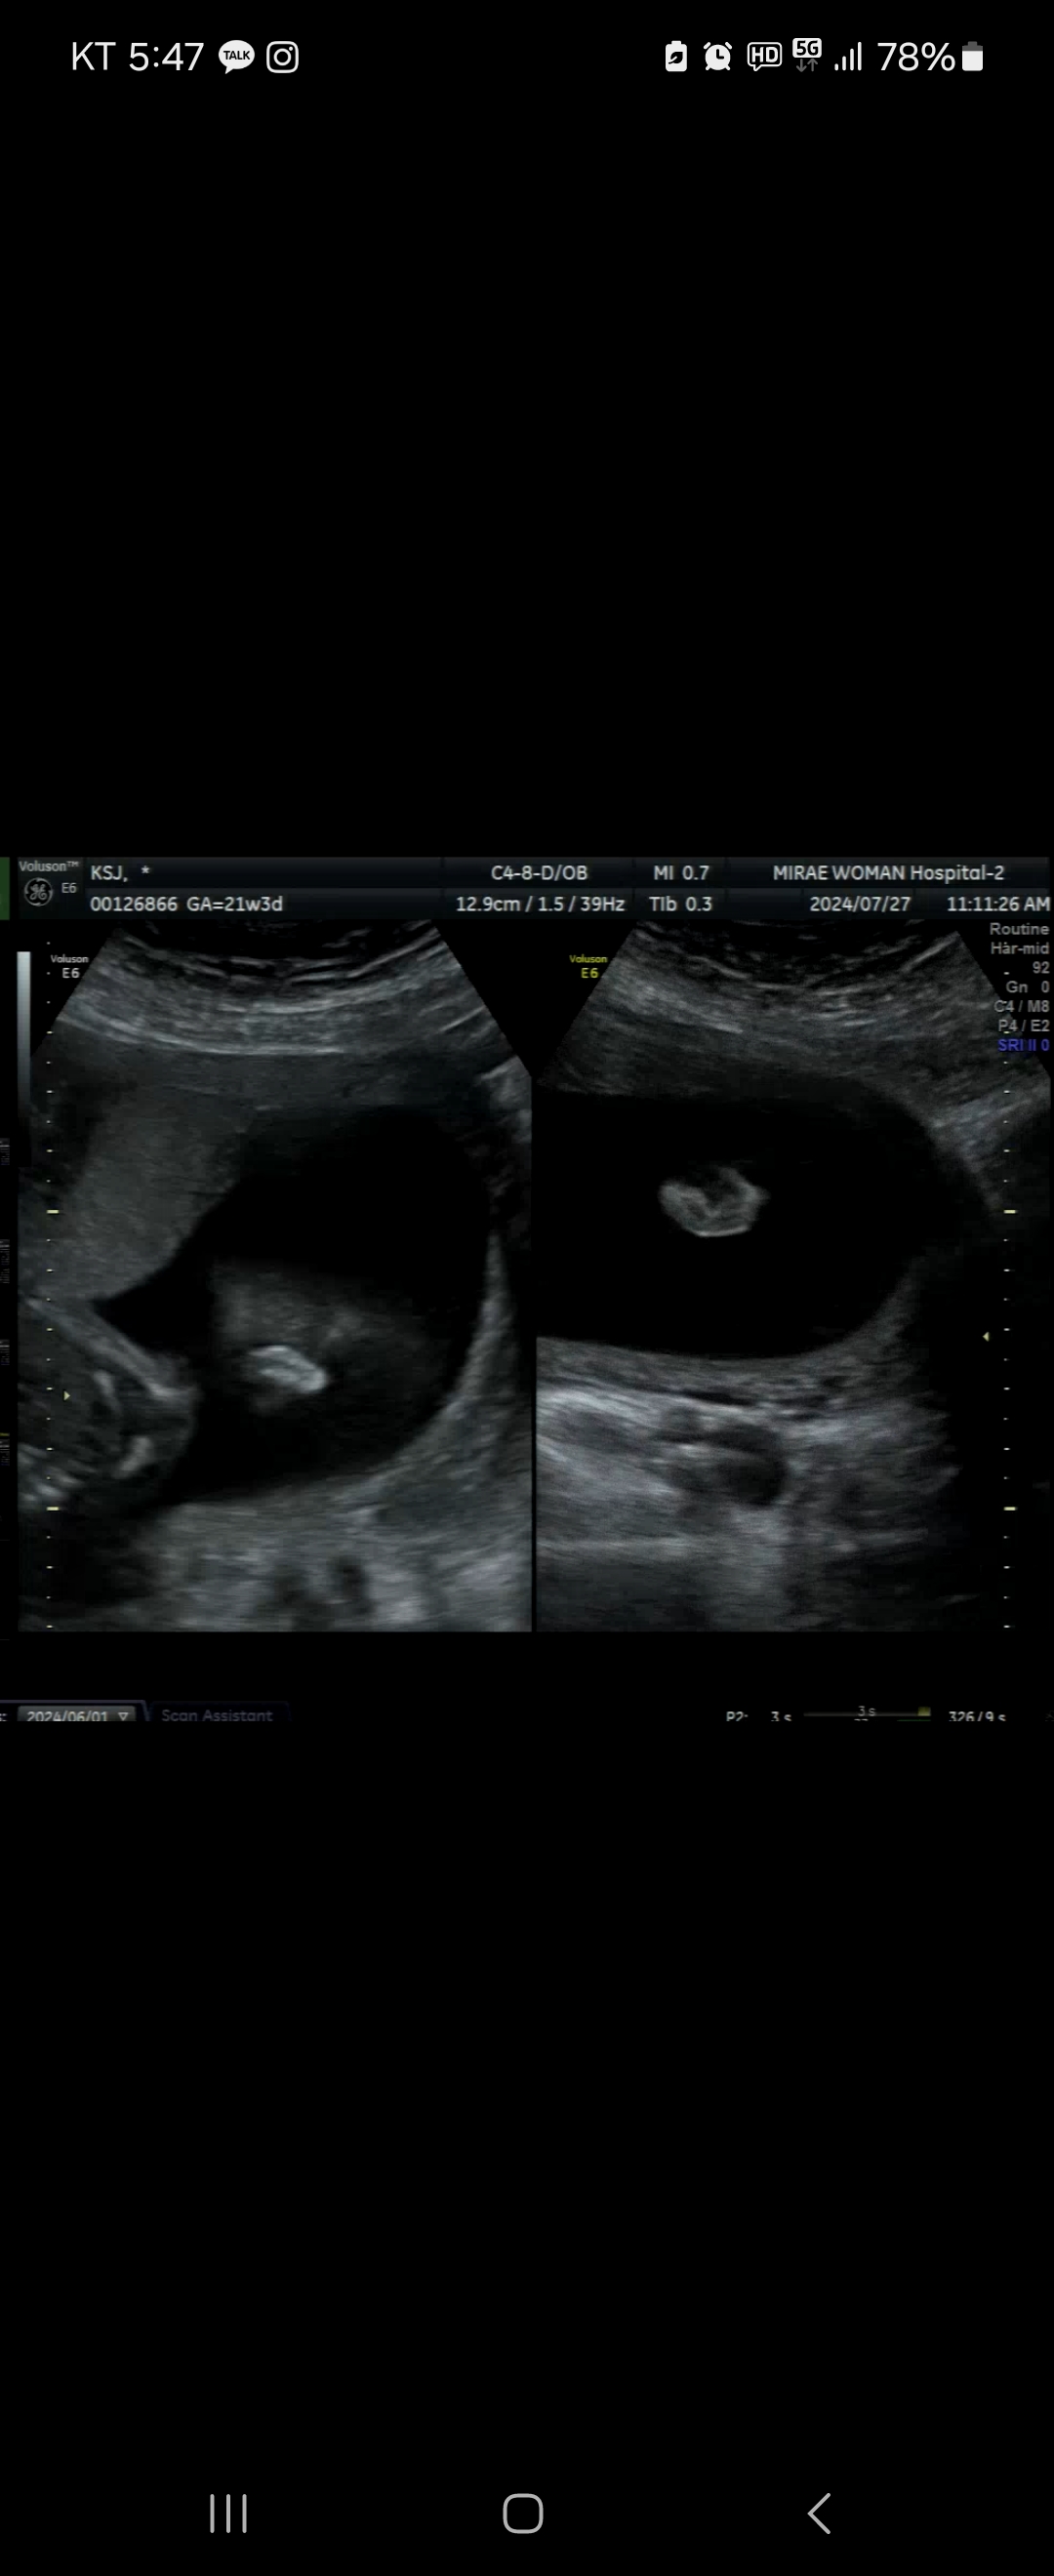

안녕하세요! 21주 4일차 초음파입니다 대학병원에서 소이증이라고 확진은 받지 않았습니다 태어나 봐야 안다고 말씀해주시고 접혀있을 수도 있다고 하시고.. 근데 사진을 보면 차이가 너무 나서 걱정이 되네요ㅠㅠ 잘 아시는 분이 계신다면 댓글 적어주시면 정말 감사하겠습니다..